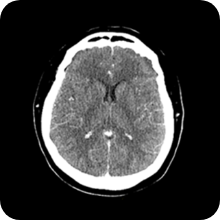

노이즈 제거 전후

전 후